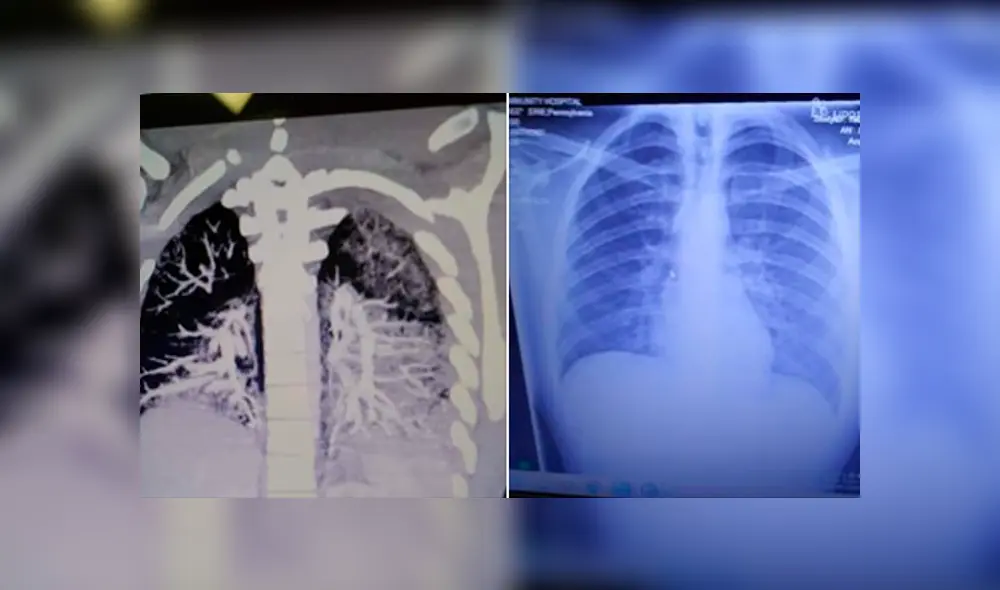

Los pulmones de Anthony estaban muy congestionados y su nivel de oxígeno era de solo un 36%, cuando cualquier cifra por debajo del 90% es considerada alarmante por los médicos. Keith Mayo, su padre, le contó a Metro UK que los médicos le advirtieron que su hijo “en este momento, a la edad de 19 años, tenía los pulmones de un fumador de dos paquetes diarios de 70 años”.

Mientras que la madre de Anthony, Tanya Marie, pidió también a través de Facebook ayuda para recaudar fondos para la recuperación de su hijo y se refirió a su estado de salud: "El pulmón izquierdo está aproximadamente en un 80% congestionado, mientras que el derecho un 50%''.